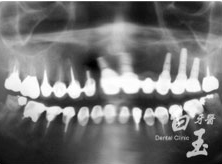

患者全口 X 光

治療前